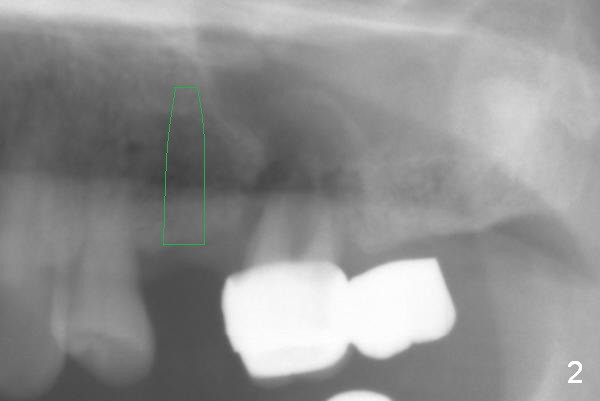

The 72-year-old man will return for #13-15 implantation after that at #2/4 and 28. There is severe wear in the cingula of the upper anterior teeth due to posterior collapse (several missing teeth, residual root and failing restoration, Fig.1). Prior to removal of the cantilever bridge (#14.15), an implant is placed at #13 (Fig.2). If the defect at #14 is too large after extraction, an implant is placed at #15 with an immediate provisional bridge (Fig.3 white line). Otherwise a large implant (possibly Tatum tapered) will be placed at #14 (Clindamycin) with splinted immediate provisional (Fig.4). Allograft is expected for sinus lift at #14 and 15 (Fig.3,4 red circles with Osteogen in 3:1 ratio). For socket preservation at #14, mix equal amount of allograft and Osteogen (Fig.3 pink), followed by Collagen plug (yellow) and the pontic of the provisional bridge. Prepare PRF (3-4 tubes of blood, one of them to be made for a plug).